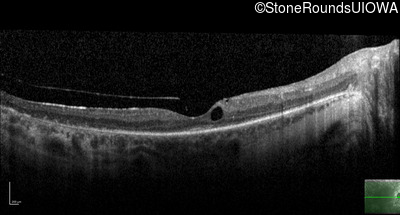

Optical Coherence Tomography - Right - 20/40 +1

Exemplar / OCT Stack